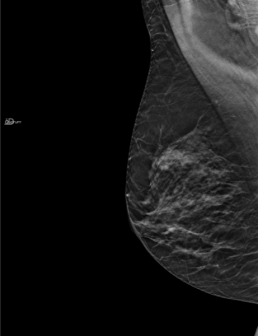

Mammographie de dépistage, interprétée comme normale sur les clichés 2D.

Mammoscreen a pu identifier, sur certaines coupes tomosynthèse, une masse sur le sein gauche, attribuant un score de 5 à cette détection. Cette masse a été à la fois détectée sur la vue de face et la vue oblique. Cette lésion a été retrouvée sur l’échographie orientée. Il s’agissait d’un cancer lobulaire infiltrant.

Ce dossier montre l’intérêt de l’IA appliquée à la tomosynthèse dans la détection de cancers subtils sans traduction évidente en 2D.